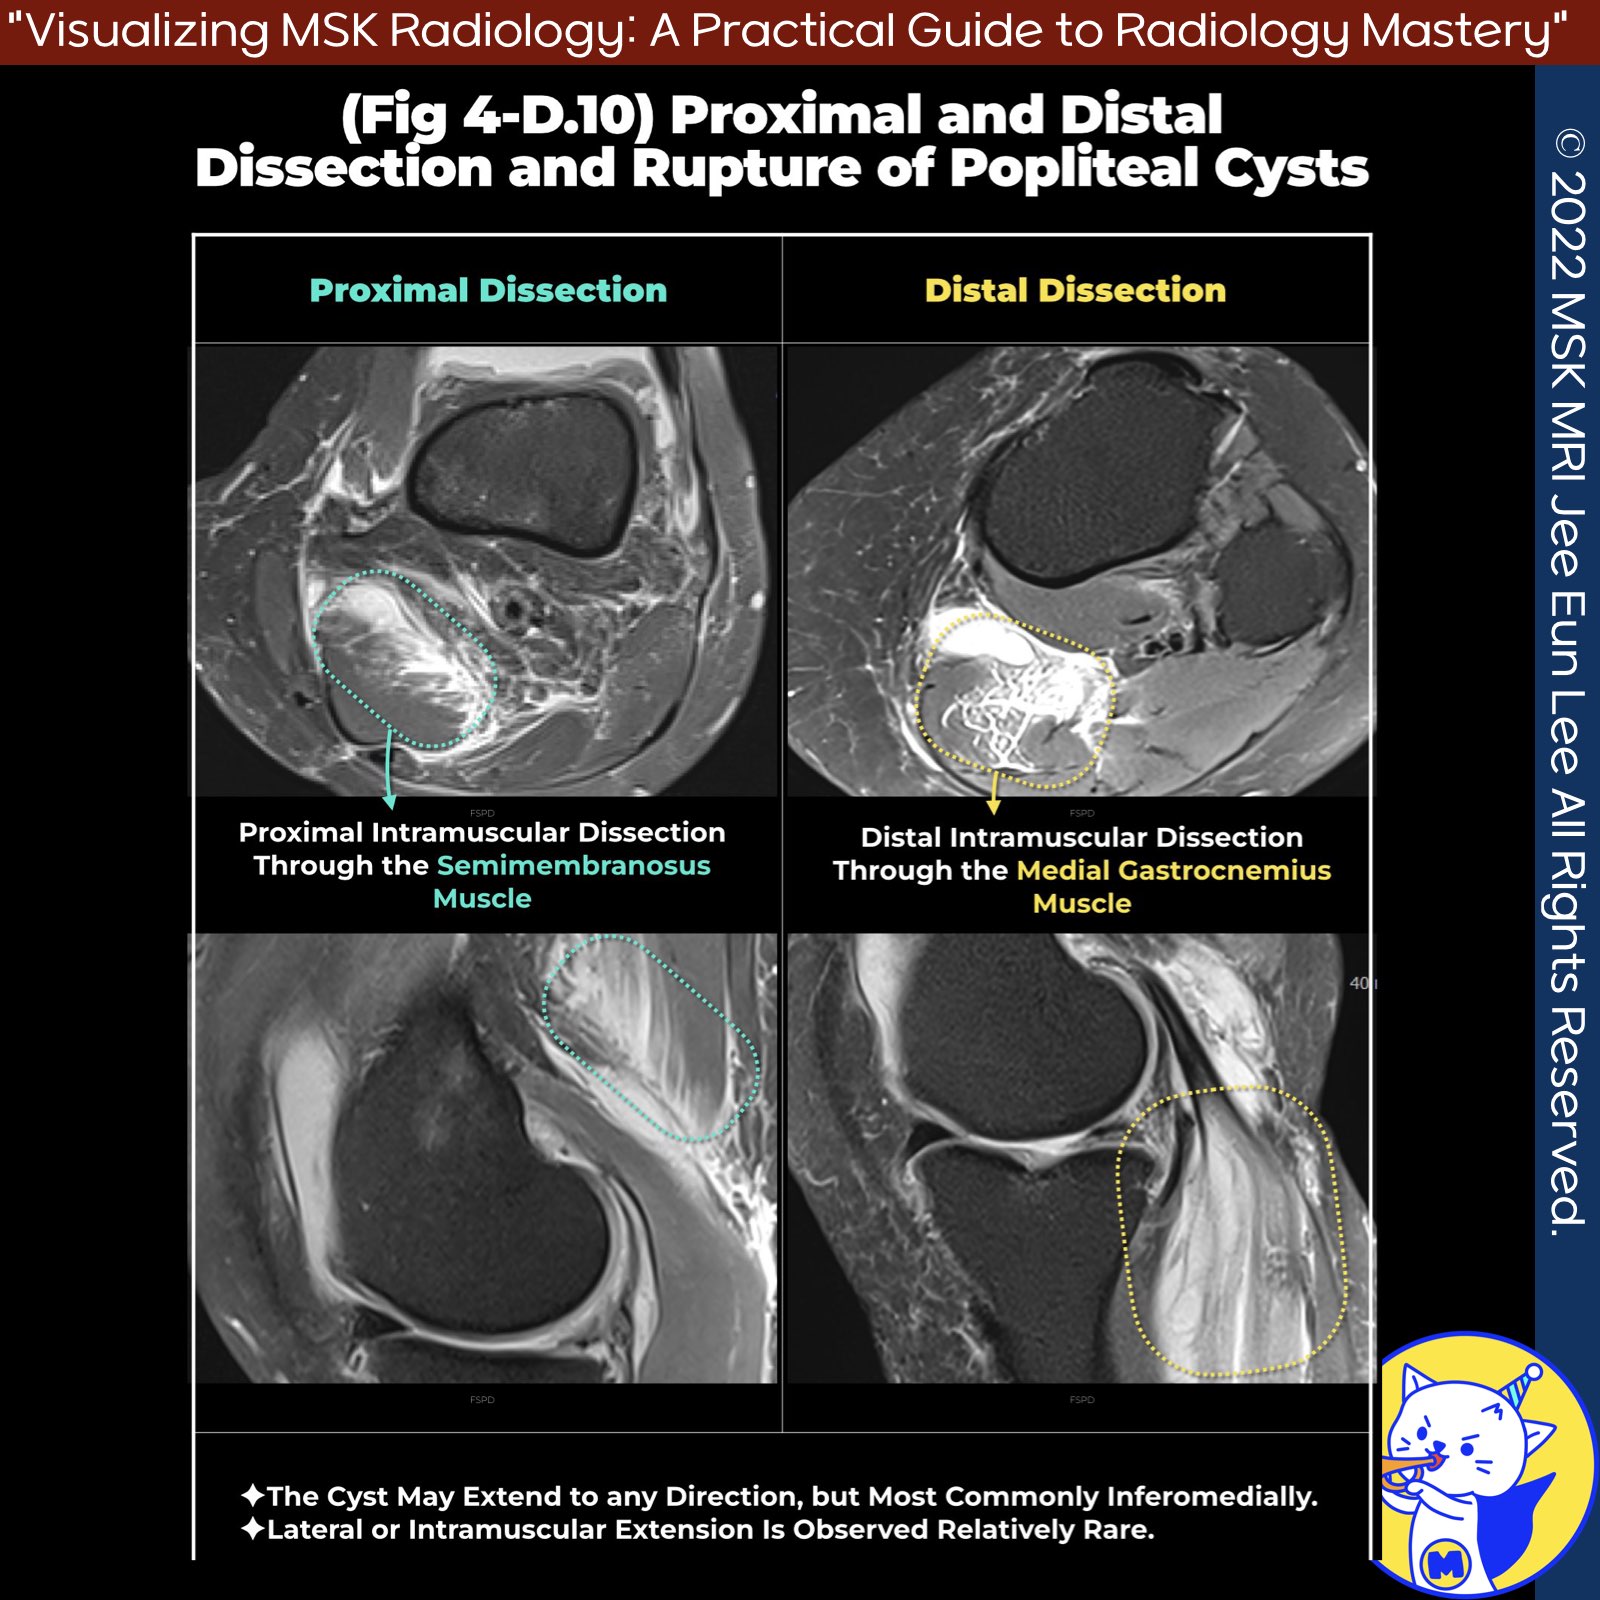

📌 Ruptured Baker's Cysts: Distal and Proximal Intramuscular Dissection

- Typical Presentation of a Ruptured Baker's Cyst: A ruptured popliteal cyst, commonly known as a Baker's cyst, usually appears as high signal intensity edema dispersing into adjacent soft tissues and fascial planes.

✅ Case 1: Distal Intramuscular Dissection

- Clinical Presentation: Tender fullness at the posteromedial aspect of the knee, just below the joint line.

- Pathology: Dissection through the medial gastrocnemius muscle, presenting outside and within the muscle compartment.

✅ Case 2: Proximal Intramuscular Dissection

- Clinical Presentation: Dissection extending superiorly into the semimembranosus muscle above the knee joint.

- Pathology: The cyst penetrates the muscle fascia and extends into the muscle.

★ Differential Diagnosis

- Both cases can mimic trauma-induced myofascial muscle tears on imaging.

- However, the key distinguishing feature is the presence of the Baker's cyst neck, which extends to the posterior aspect of the knee joint, located between the semimembranosus tendon and the medial head of the gastrocnemius.

- Identifying this structure is crucial for accurate diagnosis.